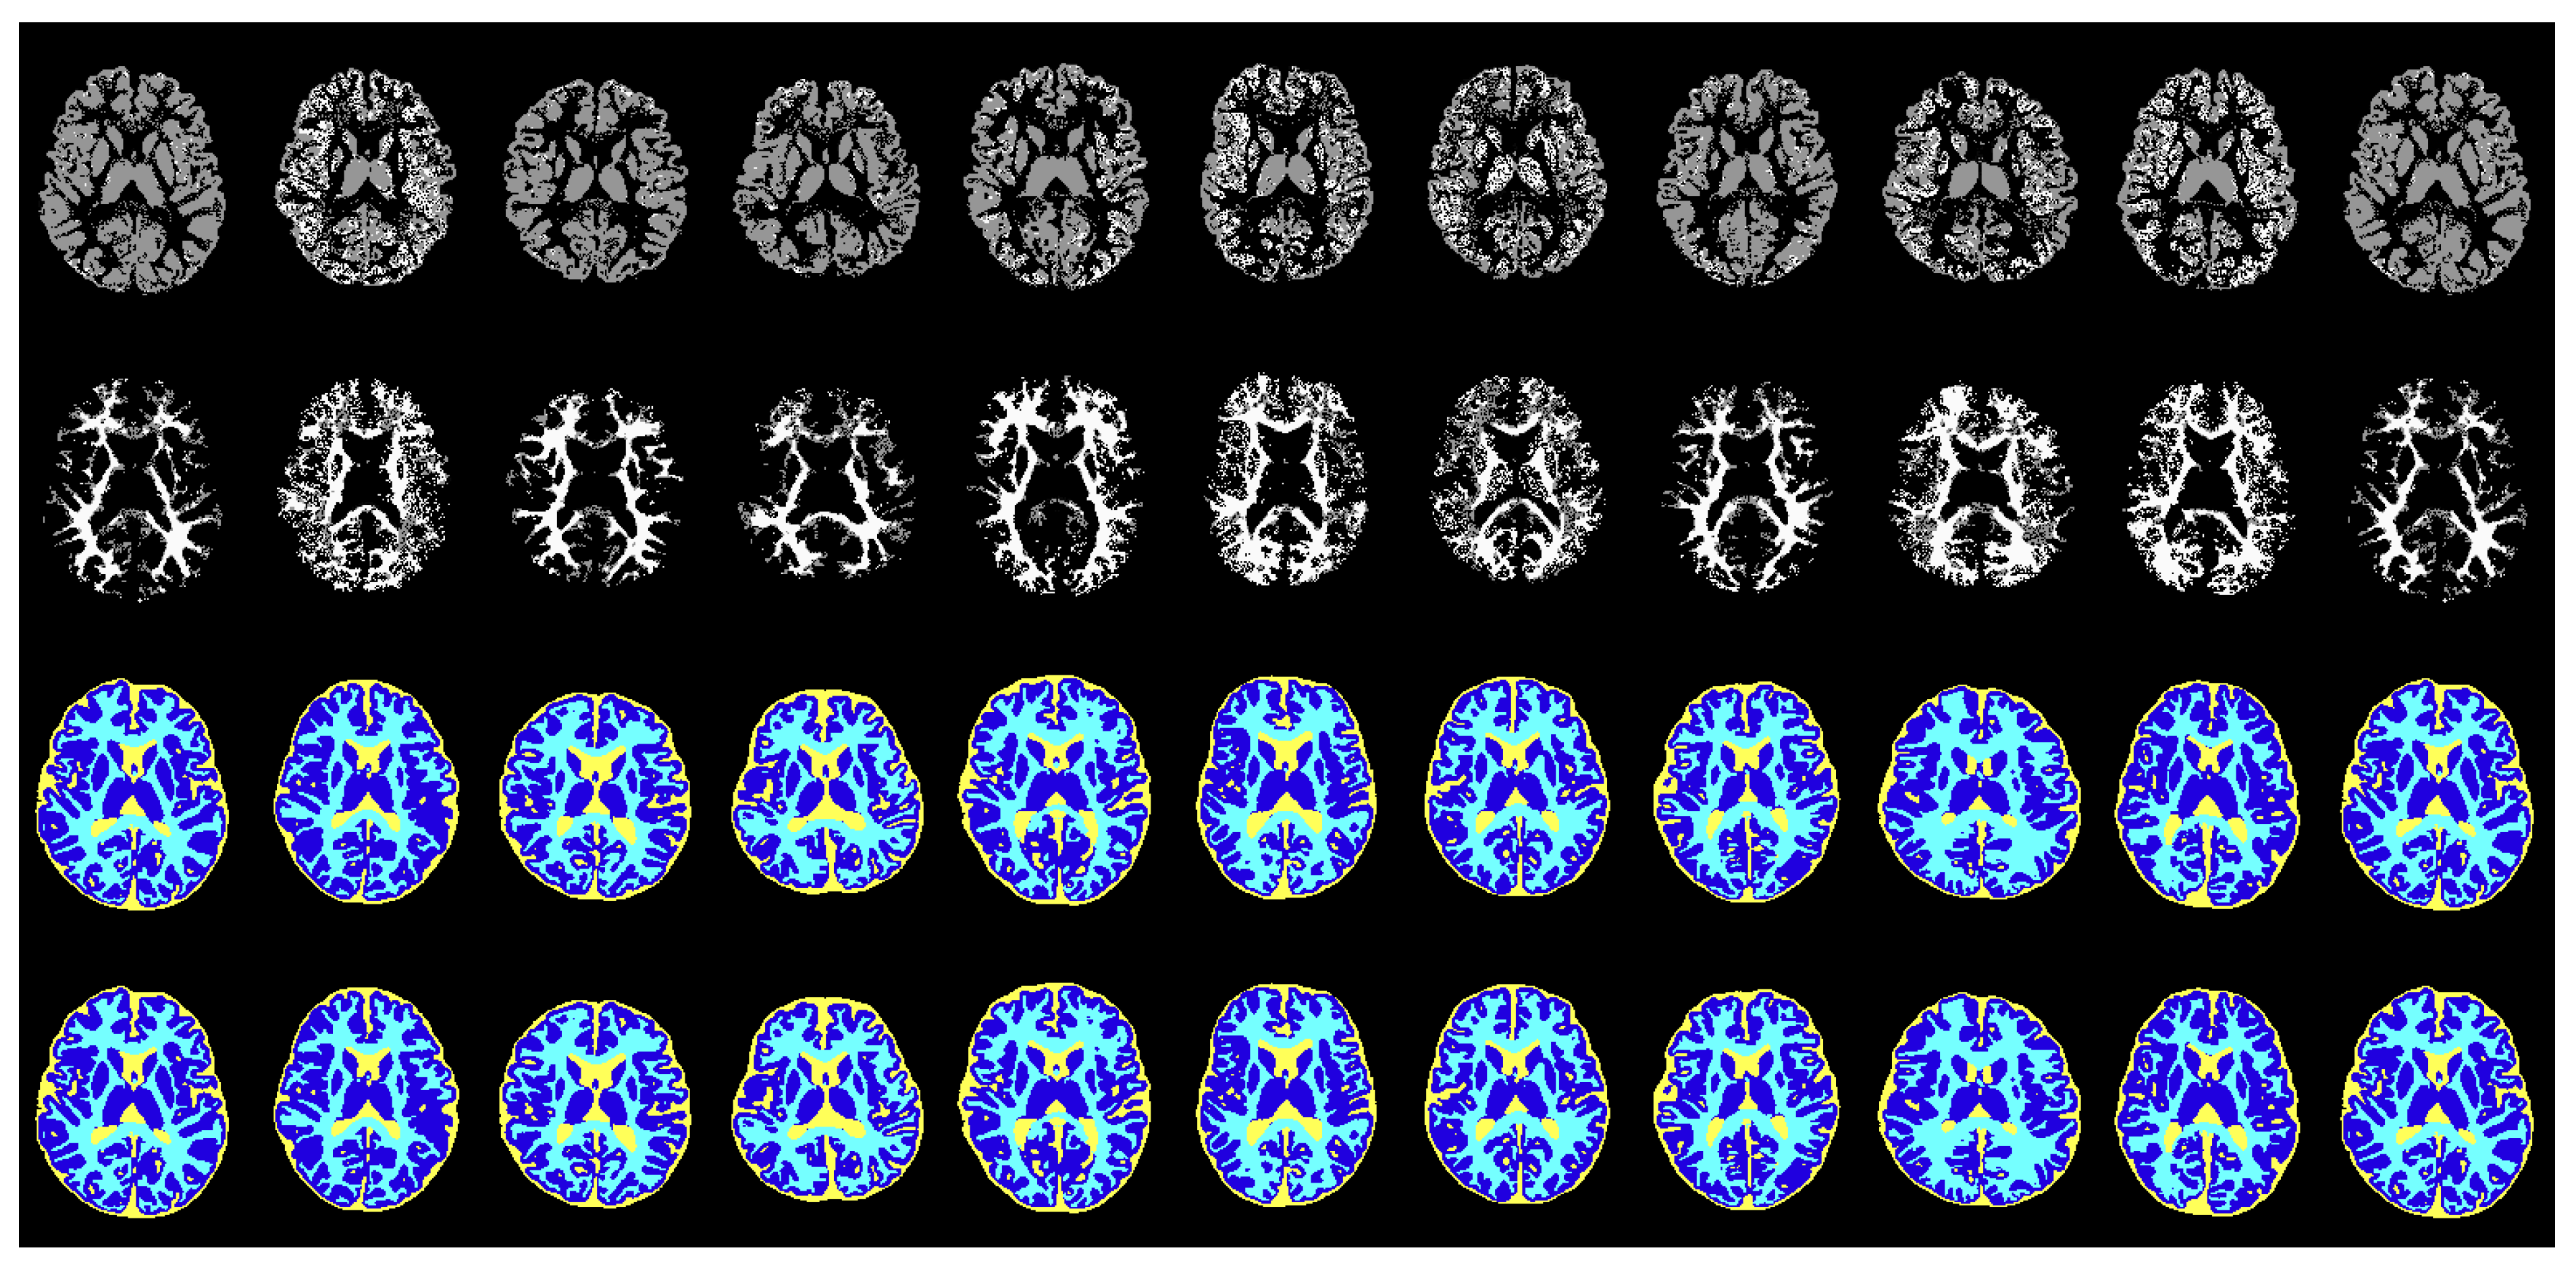

5.1. Segmentation Results